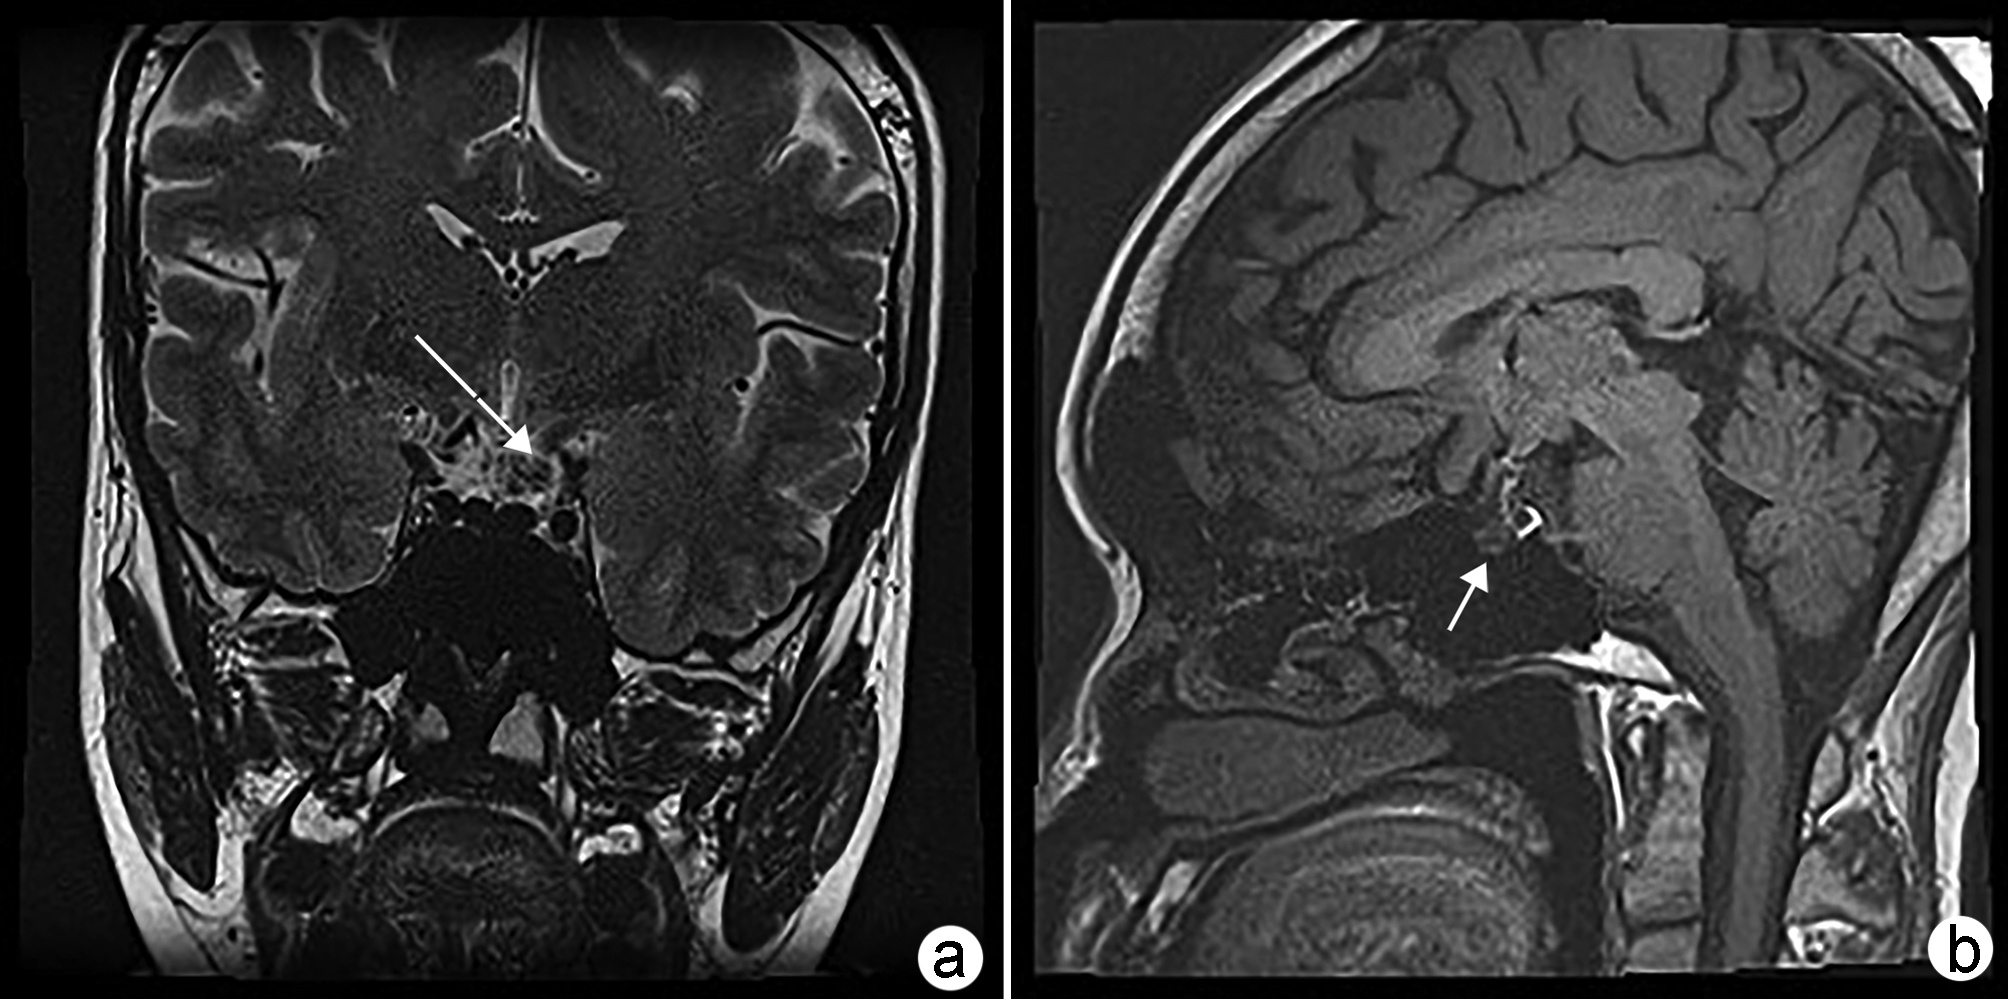

非酒精性脂肪性肝病相关认知功能损伤的危险因素

2022, 38(11): 2592-2595. DOI: 10.3969/j.issn.1001-5256.2022.11.031

摘要(861) HTML (303) PDF (1863KB)(76)

摘要:

非酒精性脂肪性肝病(NAFLD)现已成为全球最常见的慢性肝病之一。近年研究发现,NAFLD疾病进展过程中可出现不同程度的中枢神经系统功能障碍,包括认知功能损伤、情绪失衡等。本文归纳了不同阶段下NAFLD相关认知功能损伤的主要危险因素,为该病的早期预防与临床治疗提供一定依据和思路。